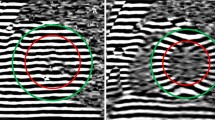

CMR techniques used for morphological and functional assessment. A: End-diastolic basal short-axis SSFP image of a healthy control, used for quantification of LV volumes and mass. B: LV basal short-axis end-diastolic HARM-image of the same patient as (A) with manually drawn epicardial (green) and endocardial (red) contours. By using Harmonic phase (HARP) analysis, myocardial deformation can be monitored throughout the cardiac cycle, allowing determination of left ventricular torsion and subendocardial circumferential strain (inner 50% of the LV wall) throughout the cardiac cycle. C: End-diastolic short axis SSFP image of a HCM mutation carrier, showing normal cardiac morphology and dimensions. D: LV short axis HARM-image of the same carrier as (C) acquired at end-systole.

From the tagging images, LV torsion was calculated as the circumferential-longitudinal shear angle using Harmonic Phase displacement tracking as described before [32, 33]. For this, endo- and epicardial contours were drawn on the harmonic magnitude (HARM) images (Figure 1) [34]. Since this method includes the radius and the length of the ventricle, torsional values are comparable between hearts of different sizes. Torsion was calculated between the basal and apical slices, between the basal and mid slices and between the mid and apical slices.

Furthermore, Lagrangian circumferential strain was calculated from the tagging images using the Harmonic Phase method as described previously [36]. Strains were assessed for the inner (subendocardial) layer of the myocardium, encompassing 50% of the LV wall. Therefore, the epicardial contour (green line in Figure 1) was automatically shifted towards the centre of the wall. Peak values were determined from the strain curves.